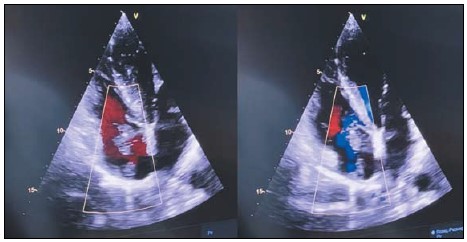

Описание клинического случая. В статье описан случай струмального карциноида яичника гигантских размеров с отдаленным метастазом в полость правого предсердия в виде флотирующего тромба и его радикального хирургического лечения, проведенного в два этапа.

Заключение. Данный клинический случай демонстрирует важность всесторонней предоперационной диагностики, интраоперационной оценки и гистопатологического диагноза. При данной патологии, протекающей чаще бессимптомно, различные диагностические обследования имеют низкую специфичность и чувствительность, и в большинстве случаев диагноз устанавливается на основании результатов послеоперационного патологоанатомического исследования.